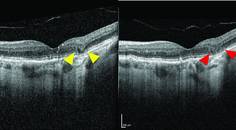

The patient tested her vision for changes and metamorphopsia at home several times a week using the ForeseeHome. In October 2020, 2 years after she started using the device, an aberration was detected. The aberration was reviewed by an in-house clinician at the Notal Vision Monitoring Center, who confirmed that it was likely not a false positive, and the referring practice was alerted. The practice contacted the patient, who returned for an in-person evaluation.

The clinical examination confirmed evidence of conversion to neovascular AMD. The patient’s BCVA had dropped to 20/40 OD, and OCT imaging revealed subretinal fluid in that eye (Figure 2). The patient was referred for retina care, and the first of three planned anti-VEGF injections was administered.